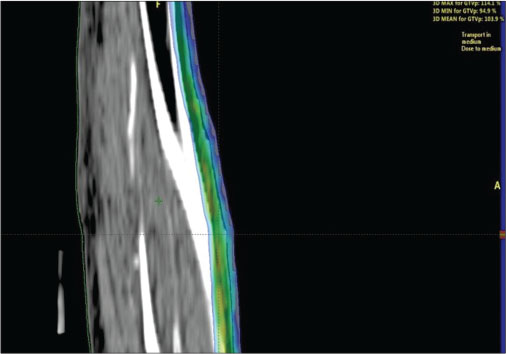

He was commenced on external beam RT (EBRT). We selected electron beam therapy as the cutaneous lesions were mostly superficial (involving the dermis and deep dermis). CT-based RT simulation was done in the supine position with left leg abducted and slightly externally rotated to keep the contralateral leg away from the electron beam. Thin axial sections CT images were acquired after intravenous contrast injection from mid-thigh to foot. Images were transferred to treatment planning system, and three-dimensional reconstruction was done. A single enface portal with 6 MeV, energy electron beam, was selected ensuring adequate coverage of the affected skin. A tissue-equivalent bolus of 5-mm thickness was also kept over the skin to deliver adequate dose to the skin lesions. Dosimetric plan evaluation with different parameters was done ensuring adequate coverage of the targets [Figure 4] and [5]. He received a total dose of 33 Gy in 11 daily fractions over 13 days. He tolerated the treatment without significant acute RT toxicity. On follow-up after 6 weeks, complete regressions of the lesions were observed without any late RT toxicity except mild hyperpigmentations over the affected area.

|?Figure. 4? Axial view

|?Figure. 5? Sagittal view